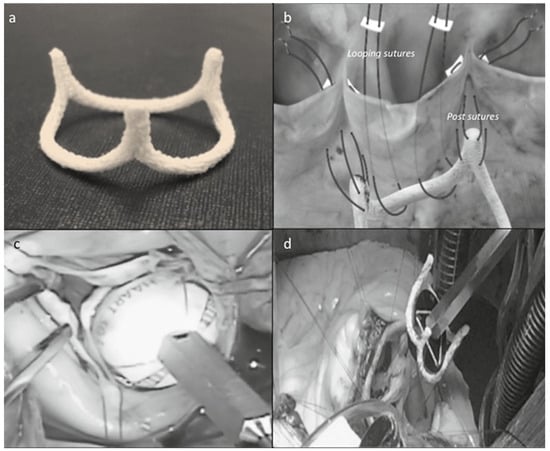

The HAART 300TM aortic annuloplasty ring (BioStable Science and Engineering, Austin, TX) was recently introduced to achieve annular stabilisation in patients with tricuspid anatomy. It was developed from mathematical analyses of normal human CT angiograms and has a 2:3 elliptical shape with three equidistant subcommissural posts, pointing 10° outwards (Figure 1a). The device is produced in four different sizes: 19, 21, 23 and 25 mm.

Figure 1.

(a) The HAART 300™ ring device; (b) schematic view of device implantation; (c) sizing procedure; (d) an intraoperative view. Photos courtesy of Prof. JS Rankin.

The ring implantation needs the positioning of three 4-0 polypropylene horizontal mattress sutures passed at the level of the subcomissural spaces and to the ring posts, in order to parachute the device 2 mm below the aortic leaflets, fixing it to the aortic annulus. Next, each ring body is anchored to the annulus by means of two separated double armed 4-0 polypropylene suture passed in order to make a loop around the ring itself (Figure 1b). The correct ring size is chosen by means of a specific ball-shaped sizing system that defines the length of the free edge of the leaflet due to a black hatched area (Figure 1c). An intraoperative view is presented in Figure 1d.